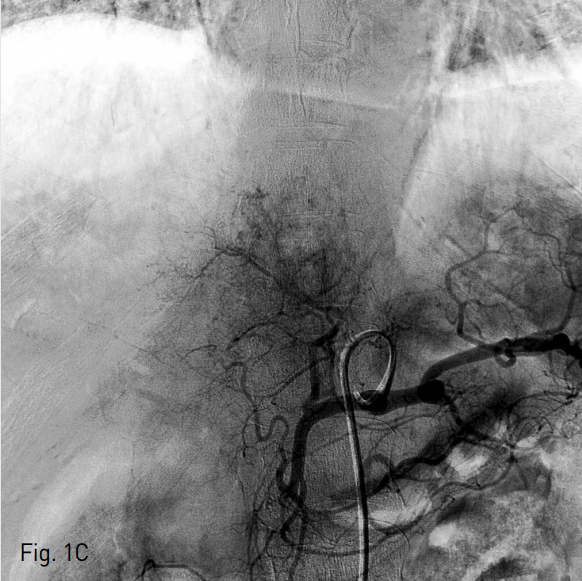

응급실 내원 직후 시행한 복부 CT에서 liver의 4,7,8 segment에 다량의 혈종과 pseudomaneurysm 그리고 multiple active bleeding이 관찰되었다 (Fig.1A). 색전술을 위하여 시행된 혈관조영술에서 replaced right hepatic artery branching off of the SMA를 통한 간 우분절에 다발성의 점상출혈이 있고 (Fig. 1B) 또한 left hepatic artery of celiac trunk를 통한 간 좌분절에도 다발성의 점상출혈이 있어 (Fig. 1C) 색전술을 시행하였다.

C. Celiac angiography revealed faint multifocal small active bleeding at the left hepatic segment of liver through the left hepatic artery.